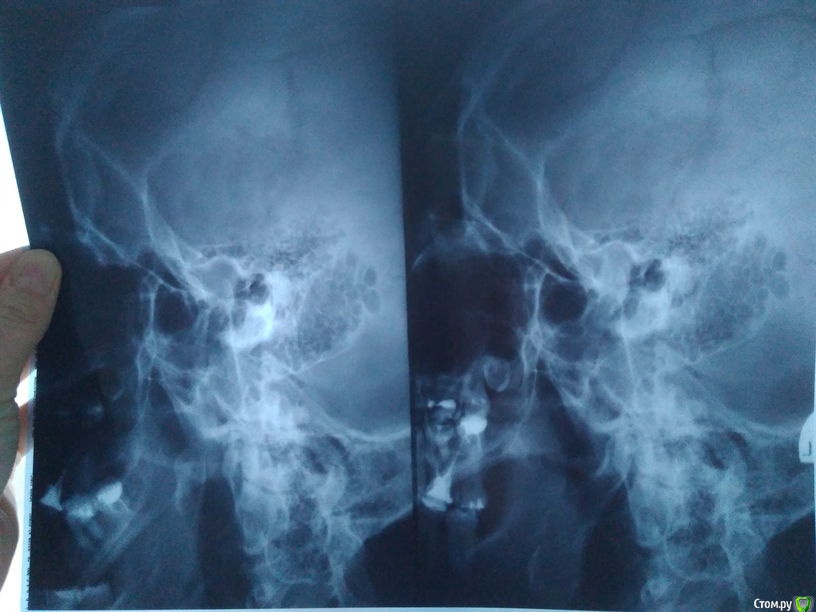

MargaritaM Опубликовано 15 января, 2018 Поделиться Опубликовано 15 января, 2018 Здравствуйте! Ранее я к Вам обращалась за советом - http://forum.stom.ru/topic/33953-verkhnie-retinirovannye-vosmerki-zuby-mudros/ Пол - женский, сейчас 29 лет конец 2016 годаВосьмерку удалили, всё прекрасно зажило. Шестерку перелечили - оказалось предыдущий доктор недоработал и как следует не заделала каналы, к сожалению, один из 3х каналов был испорчен предыдущим доктором и его не удалось пройти до конца. К сожалению, на этом злоключения не закончились. конец 2017 года - начало 2018 годаПрошел год и опять вернулись боли справа. В ноябре-декабре 2017 начала ныть 7ка, её обработали на тему чувствительности, вроде стало полегче. И вот 3 января стало болеть где-то в районе верхних правых 6ки и 7ки, реакции на накусывание или горячее/холодное нет, боли ночью усиливаются, из-за этого могла уснуть только к 3-5 утра.Пошла к доктору, зубы тестировали на холод, постукивание. 9го удалось найти кликику, где бы делали ЭОД. К тому моменту стало болеть и в области нижней 6ки. ЭОД показал, что выше нормы только в нижней правой шестерке, верхняя 7ка в норме, верхнюю 6ку не проверяли, т.к. она депульпирована. Сняли пломбу в нижней 6ке - дно белое, плотное, пульпа не обнажена, поставили временную пломбу. Около верхней шестерки изменений десны, вроде нет, цвет нормальный.Отправили к неврогологу, т.к. проблем с точки зрения зубов не нашли. К 11 января уже вся голова болит, справа болит сверху и снизу, постоянно, боль в течение дня не уходит, но к ночи сильнее. Невролог поставила диагноз: "невропатия тройничного нерва справа неуточненного генеза". И на приему невролога меня просят широко открыть рот и я тут понимаю, что мне немного больно это делать. Справа у уха болит косточка при нажатии. Если не нажимать - не болит. Болела ли она до этого - не знаю, т.к. не приходило в голову туда нажимать. Общее:- Хотела бы отметить, что жалобы на верхние шестерку-семерку-восьмерку были примерно с 2013-2014 года и имели (как сейчас понимаю) сезональный характер - жалобы в период с ноября по март, потом боль стихала. Сейчас впервые так нестерпимо больно, что уже не спишешь на чувствительность зубов.- Косточка справа у уха болела и ранее при нажиме (но изредка, непостоянно) лет с 15, но т.к. это редко, несильно и только при нажатии, то я не обращала на это внимания.- Муж говорит, что ночью зубами не скрежещу. На сегодня была у следующих докторов и версия событий такова: Невролог - невропатия тройничного нерва справа неуточненного генеза Отоларинголог - дисфункция височно-нижнечелюстного сустава справа Основной лечащий стоматолог-терапевт и коллега - дело не в зубах, нужен нейростоматолог Стоматолог-терапевт, к которому направили для независимого суждения: скорее всего, дело в верхней шестерке, недолечили канал и не нашли 4й канал. После немисила и карбамазепина стало намного легче. Днем немного побаливает, ночью может усилиться, но те страшные боли ушли. Динамика положительная - с каждым днем легче, после приема лекарст прошло 3.5 дня. На текущий момент не совсем понятно, к кому идти лечиться и в чем проблема (и есть ли она вообще).В приложении ОПТГ, снимок ВНПЧ, фото прикуса. Ссылка на комментарий

MargaritaM Опубликовано 31 января, 2018 Автор Поделиться Опубликовано 31 января, 2018 В итоге, после консультации в ЦНИИС и плюс мой невролог консультировалась (с её слов) с коллегой, они сошлись на мнении, что проблема со стороны невралгии из-за сустава. МРТ или ещё чего по ВНЧС не делали, т.к. по ДМС не понятно, кто направляет и кто умеет это адекватно читать. Поэтому решили остановиться на курсе целебрекса и шапке-ушанке в холода, и для гимнастики прописали жевать жвачку. Тьфу-тьфу, стало лучше. Если с точки зрения практики интересно, то могу периодически писать о прогрессе в данной теме. Также буду рада советам, чтобы в случае повторения обострения идти по короткому пути, к какому врачу правильнее идти (интересует направление, специальность). И вопрос - если бы это действительно зуб, то помог бы мне целебрекс? Спасибо за помощь! Ссылка на комментарий